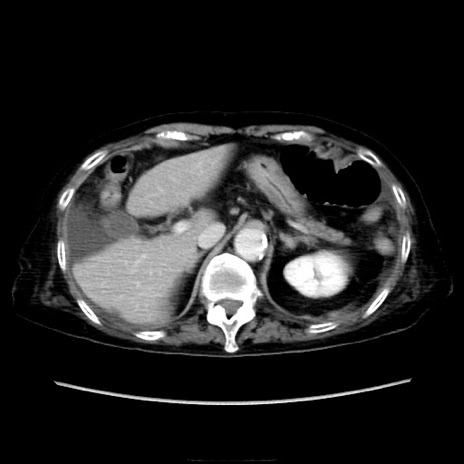

症例40(横断像)

他院CT

横断像